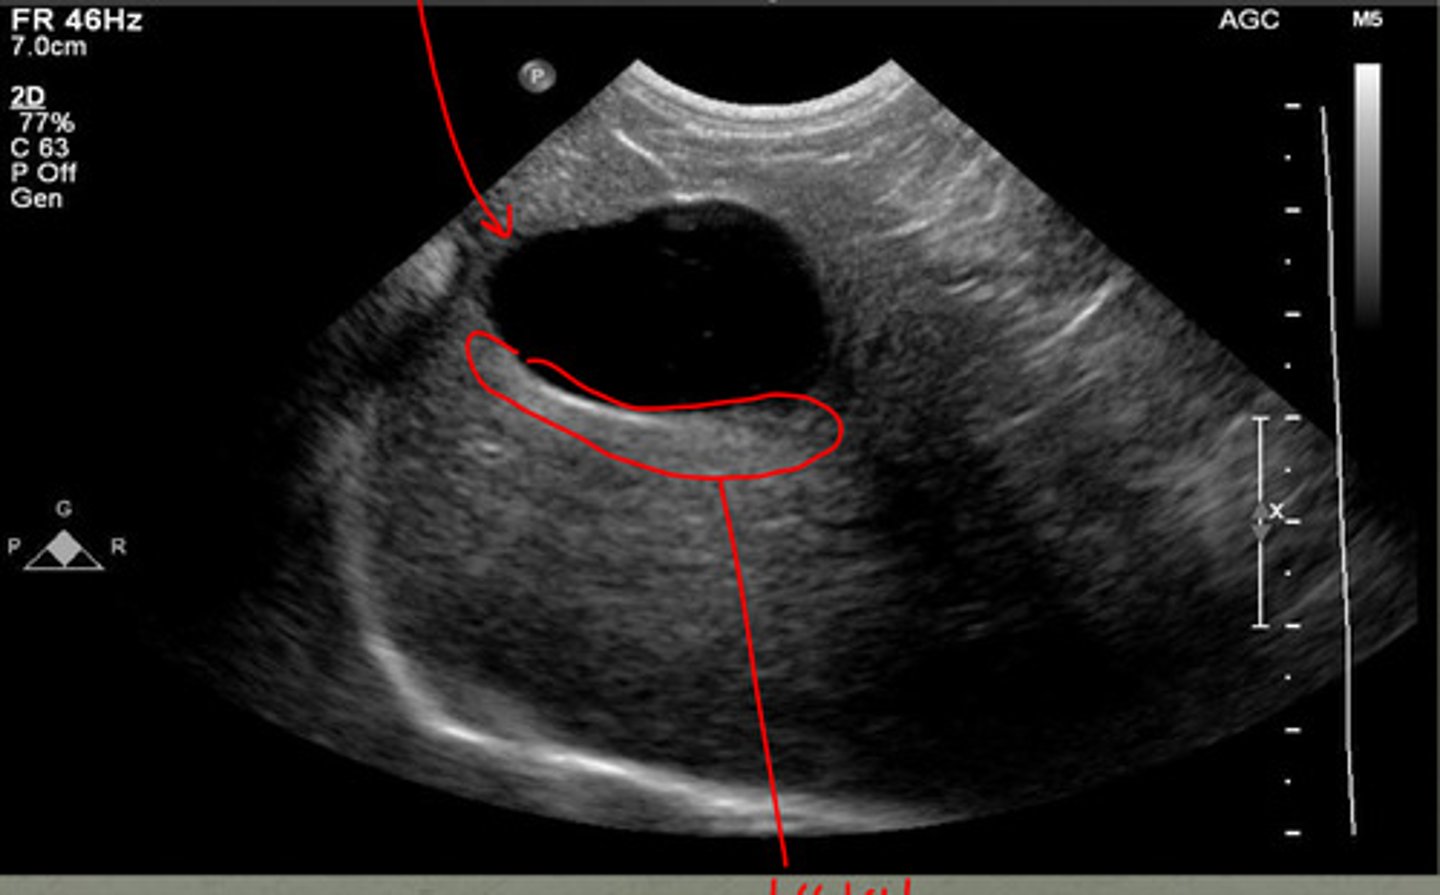

echogenicity- anechoic

shape- tear drop

how does the gallbladder appear on ultrasound? (echogenicity and shape)

the right side of the liver

where is the gallbladder located in respect to the liver?

1

the wall of the gallbladder is usually less than ____ mm in cats and dogs

anechoic

normal bile is what echogenicity?

biliary sludge or concretions

what is the echogenic material in the gallbladder?

gallbladder

if this US image was taken on the right side of the liver, what structure would this be?

distal enhancement

what artifact is the red circle indicating underneath the gallbladder?

-distal acoustic enhancement

-refraction

what are the two artifacts associated with the gallbladder?

increases echogenicity in liver parenchyma deep to gallbladder

what does distal acoustic enhancement do?

bending artifact at edges of gallbladder, seen at curved surfaces

what is refraction artifact?

star- distal enhancement

arrow- refraction

does the star or arrows show distal enhancement or refraction?